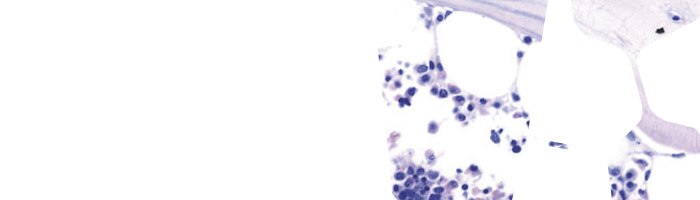

Hematoxylin Solution Acc. to Gill

Gill’s hematoxylin staining solutions are designed for use in Histology and Cytology applications. They are prepared using hematoxylin at Certistain® quality. Their perfectly balanced formulation means that they require no filtration prior to use.

Gill’s hematoxylin staining solutions are designed for use in Histology and Cytology applications. They are prepared using hematoxylin at Certistain® quality. Their perfectly balanced formulation means that they require no filtration prior to use.